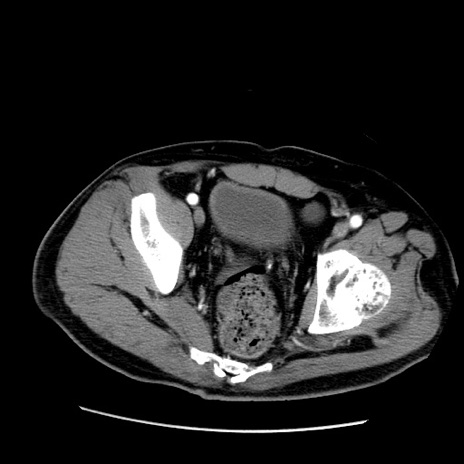

症例22(横断像)

【症例】50歳代男性

【主訴】腹痛

【現病歴】AVMからの被殻出血のため回復期リハ病棟入院中。 本日午後3時頃急に下腹部痛が出現した。

【既往歴】AVM、被殻出血、虫垂炎、高血圧

【身体所見】意識晴明、左半身不全麻痺、会話の理解は良好、36.5°C、腹部:膨隆、全体に板状硬、下腹部正中に圧痛点あり、反跳痛-、筋性防御不明、右下腹部にope scar

【データ】WBC 9400、CRP 0.06